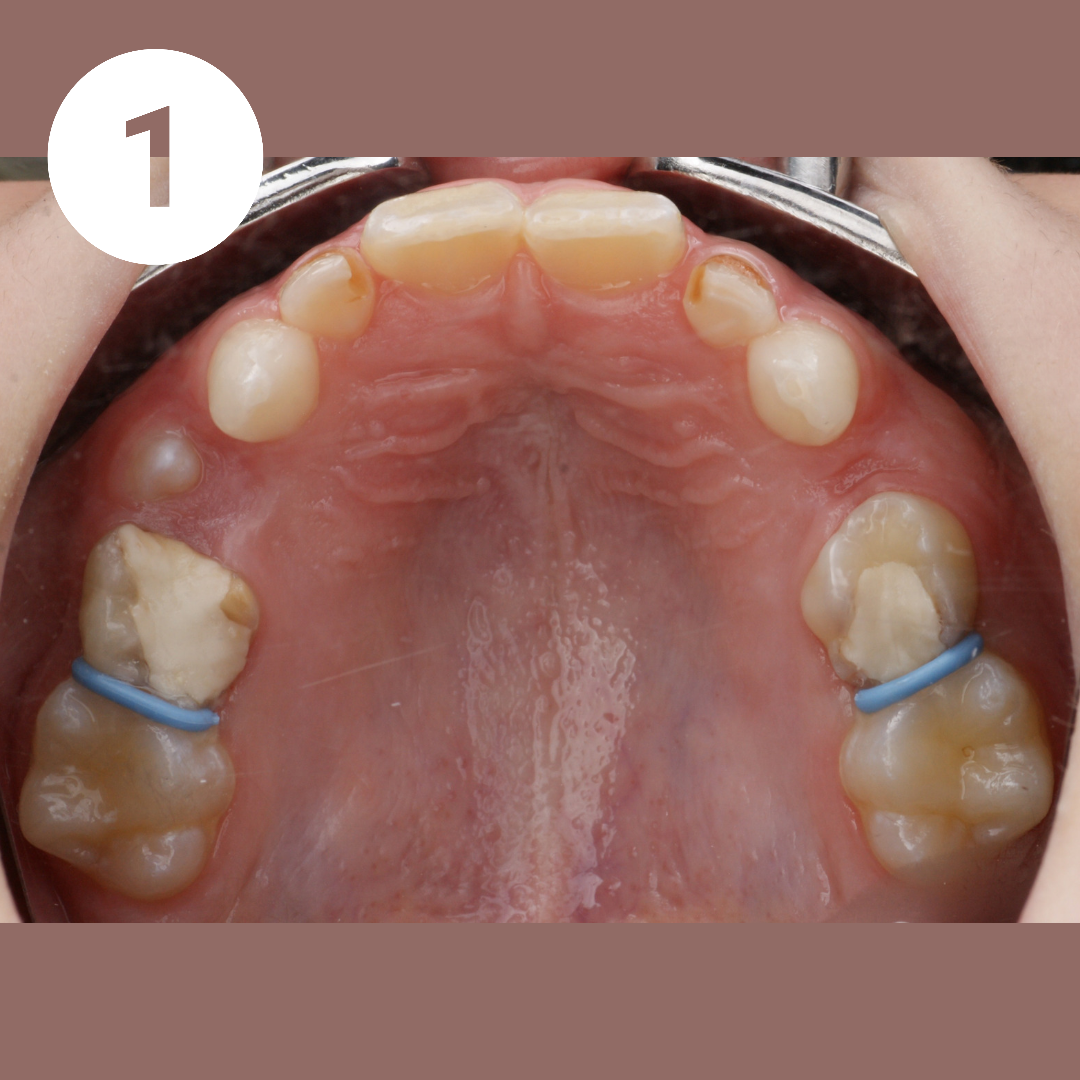

КАК УСТАНАВЛИВАЕТСЯ АППАРАТ МАРКО РОСА (Marco Rosa)

1️⃣ Установка сепарационных колец (голубые резиночки) в промежутки между опорными зубами для их небольшого раздвижения друг от друга и создания места для колец аппарата. Устанавливаются на 10-20 минут (могут устанавливаться на несколько дней).

2️⃣ Очистка опорных зубов от налёта с помощью специальной пасты и вращающейся щеточки бормашины.

3️⃣ На кольца наносится специальный стоматологический клей. Аппарат фиксируется во рту. Клей отверждается световой лампой. Добавляется клей на лапки молочных клыков.